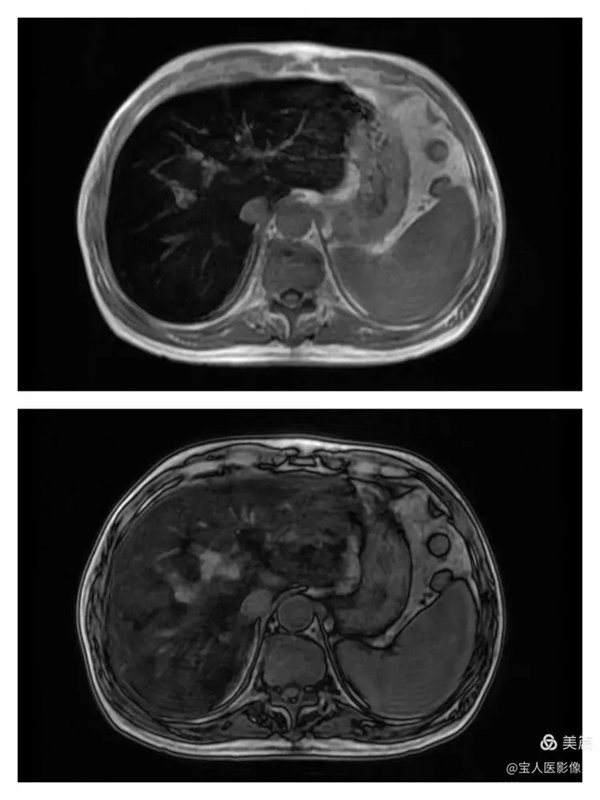

R2*圖,肝實質信號不均勻明顯升高。

R2*圖,測量全肝不同部位肝實質的R2*值都明顯升高。